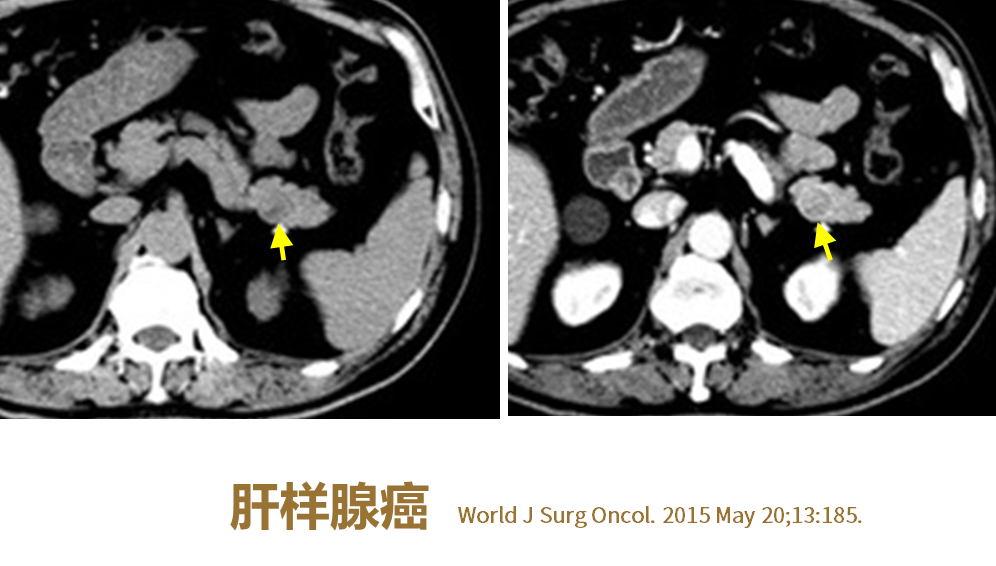

4、肿瘤标记物与恶性胰腺肿瘤

图3:富血供胰腺癌 M/53,体检发现CA-199并持续升高(肿瘤标记物为诊断重要依据)

(图片来源:余日胜教授讲课使用)

•CA199升高:

胰腺癌(包括特殊类型如腺鳞癌)、MCN及IPMN恶变

•CA199很少升高:

腺泡细胞癌、淋巴瘤

•AFP:

胰母细胞瘤(少数)、腺泡细胞癌(27%)、肝样腺癌(60%)

•CEA:

晚期胰腺恶性肿瘤